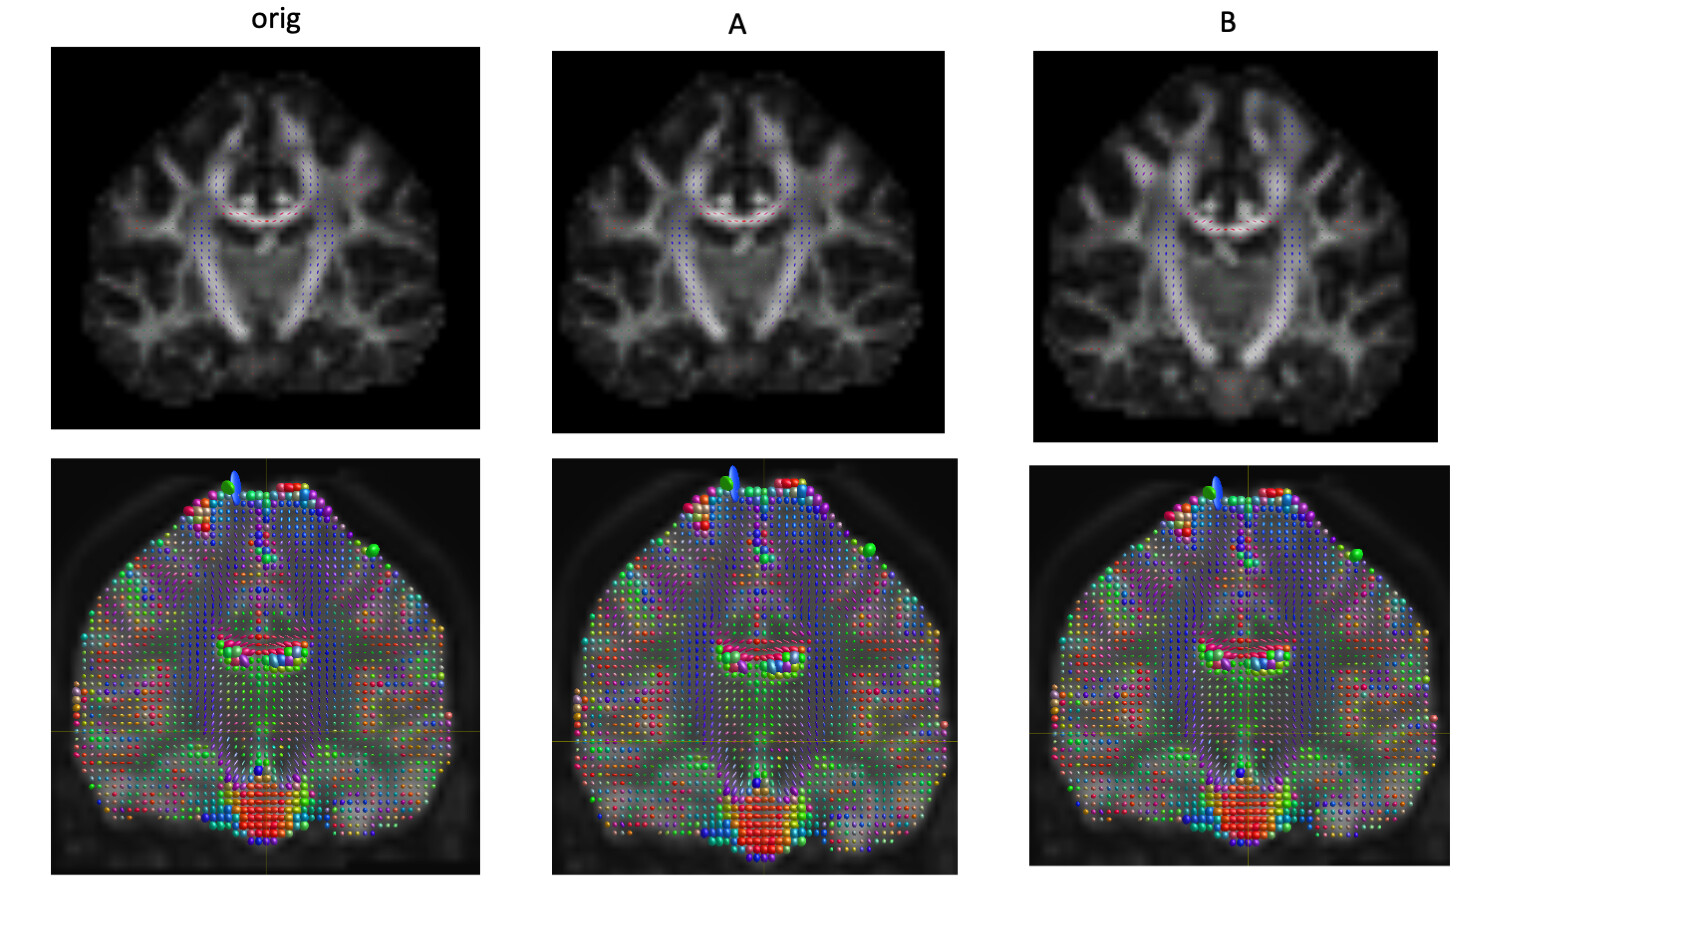

In the following text, I will use A to represent image whose stride is [1,2,3,4] after mrcovnert. Orig represents original image. I will use B to represent image whose stride is [-1,2,3,4] after mrconvert. The tensor visualization is shown in the following image

. I notice Orig and A for TORTOISE is correct but B is not correct. And Orig, A and B doesn’t work with MRtrix. I am not sure do I do something wrong ? The following is the mrinfo for Orig image.

OK, assuming the top row is TORTOISE, and the bottom row is MRtrix, the issue matches what I expected. It’s far from trivial unfortunately, due to the idiosyncrasies of the bvecs/bvals format. The main issue relates to this small, but important addition to the FSL wiki where they describe how to interpret these files (my emphasis):